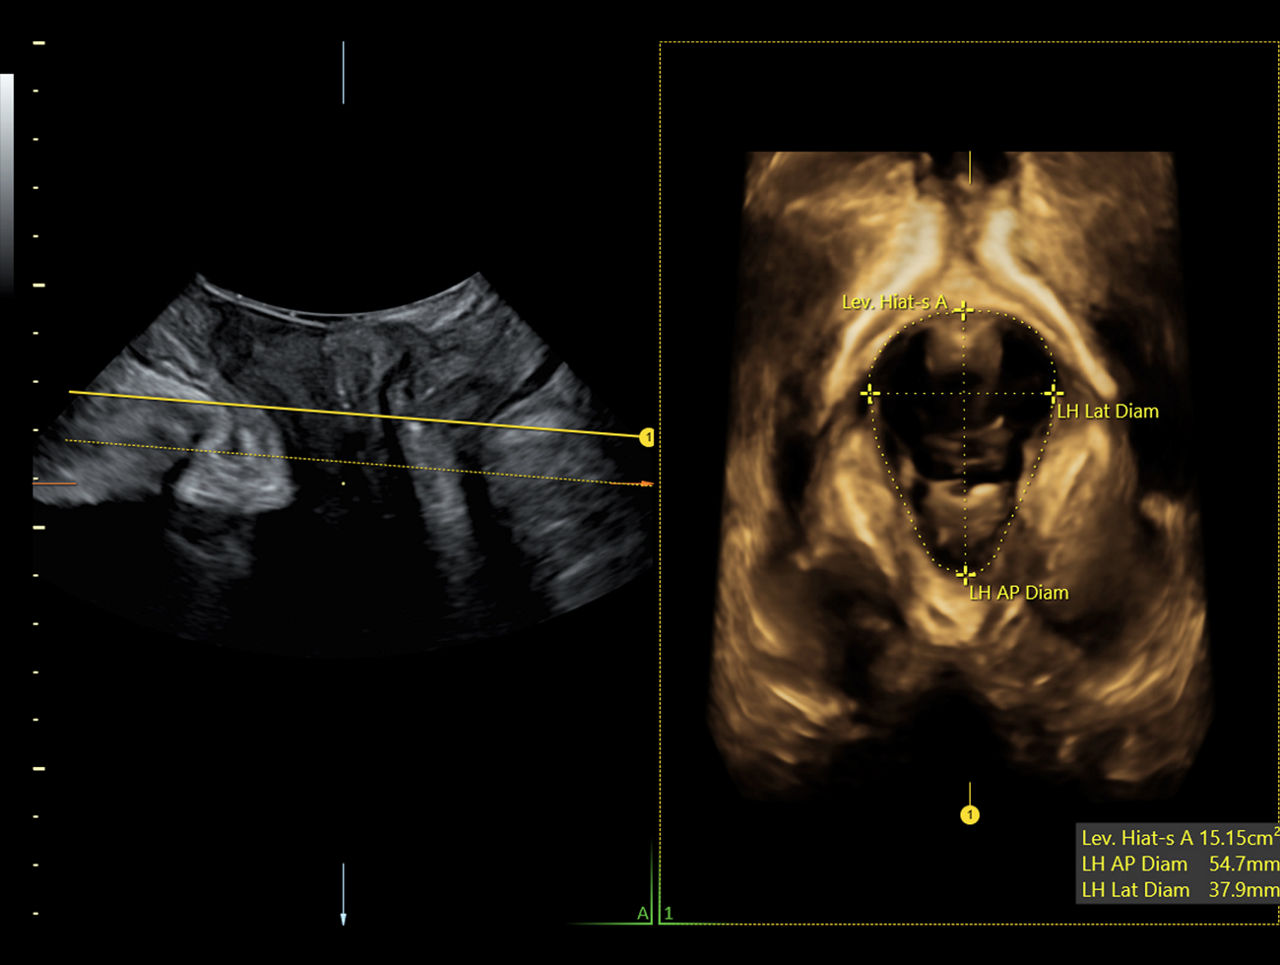

Analysis of the pelvic floor anatomy can be complicated. Through AI, SonoPelvicFloor3.0 simplifies the exam process by automating, plane alignment, live C-plane tracking, and measurements while offering workflow guidance to improve efficiency while eliminating uncertainty.

SonoPelvicFloor